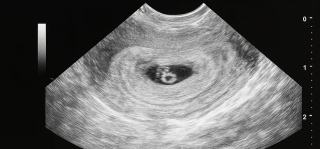

Було виконано перенесення одного ембріона. Вагітність настала з першої спроби, попри складні діагнози і попередній досвід.

На момент настання вагітності Ірині було 32 роки. Після тривалого шляху це стало підтвердженням того, що навіть у складних клінічних випадках шанс на батьківство існує.